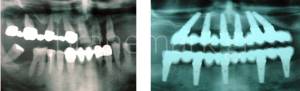

Unlike conventional dental implant techniques, which require months of healing before final teeth can be attached, the Brånemark Osseointegration Center Greece offers a cutting-edge solution: immediate loading dental implants. This advanced method allows both the implant and the new teeth to be placed in between 24 to 48 hours.

This means patients can literally walk into our clinic and leave just hours later with a fully restored, confident smile. With an impressive 98% success rate, this technique delivers long-lasting results—implants typically remain securely in place for a lifetime, often until the patient’s natural passing.

Immediate implant placement is a modern dental technique in which an implant is inserted directly after tooth extraction. In many cases, we are able to remove a damaged tooth and place a dental implant on the very same day, significantly reducing treatment time and accelerating the smile restoration process. In select situations, it is even possible to attach a new tooth to the implant immediately—something that traditionally required several months and multiple dental visits.